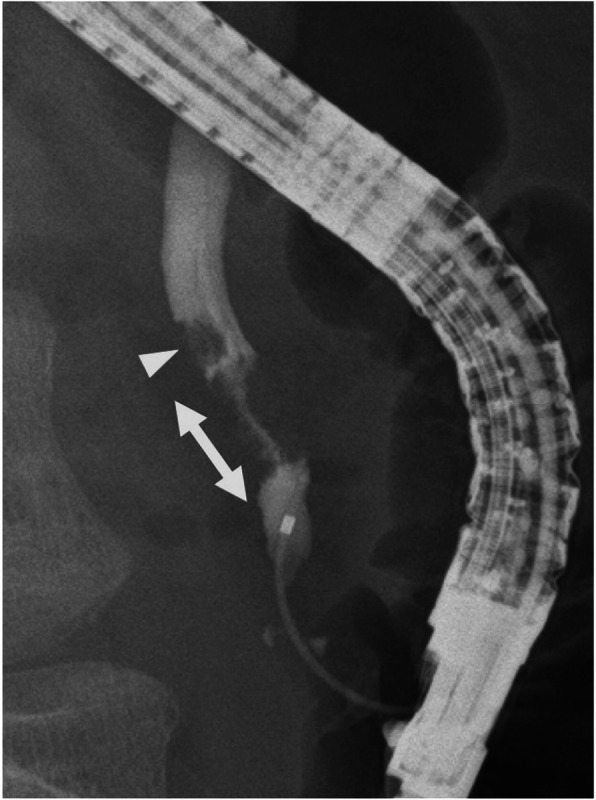

Abdominal contrast-enhanced computed tomography (CT) showed a slightly dilated CBD and a high-density spot in the DBD, suggesting a CBD stone (Fig. 1). Endoscopic ultrasonography demonstrated an elevated lesion on the DBD (Fig. 2). Permeation to the pancreatic parenchyma or to the outside of the bile duct wall was unclear. Endoscopic retrograde cholangiopancreatography (ERCP) revealed a circumferential stenosis 11.8 mm distal from the ampulla of Vater and a 5.1 × 6.5 mm irregularly shaped, elevated lesion on the DBD (Fig. 3). A double pig-tail catheter (7 Fr, 6 cm) was inserted in the bile duct. Brush cytology showed atypical ductal cells, indicating adenocarcinoma (AC) of the DBD.